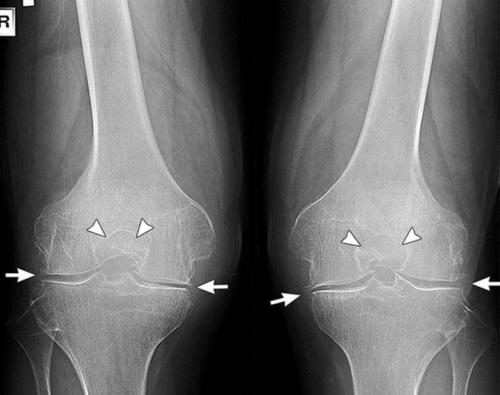

Двухстороннее отсутствие суставной щели.

Так выглядит на рентген-снимках артроз коленного сустава, упражнения для которого еще могут быть актуальны, потому что суставная щель не исчезла полностью.

На этом снимке суставу справа уже никакая гимнастика не поможет.